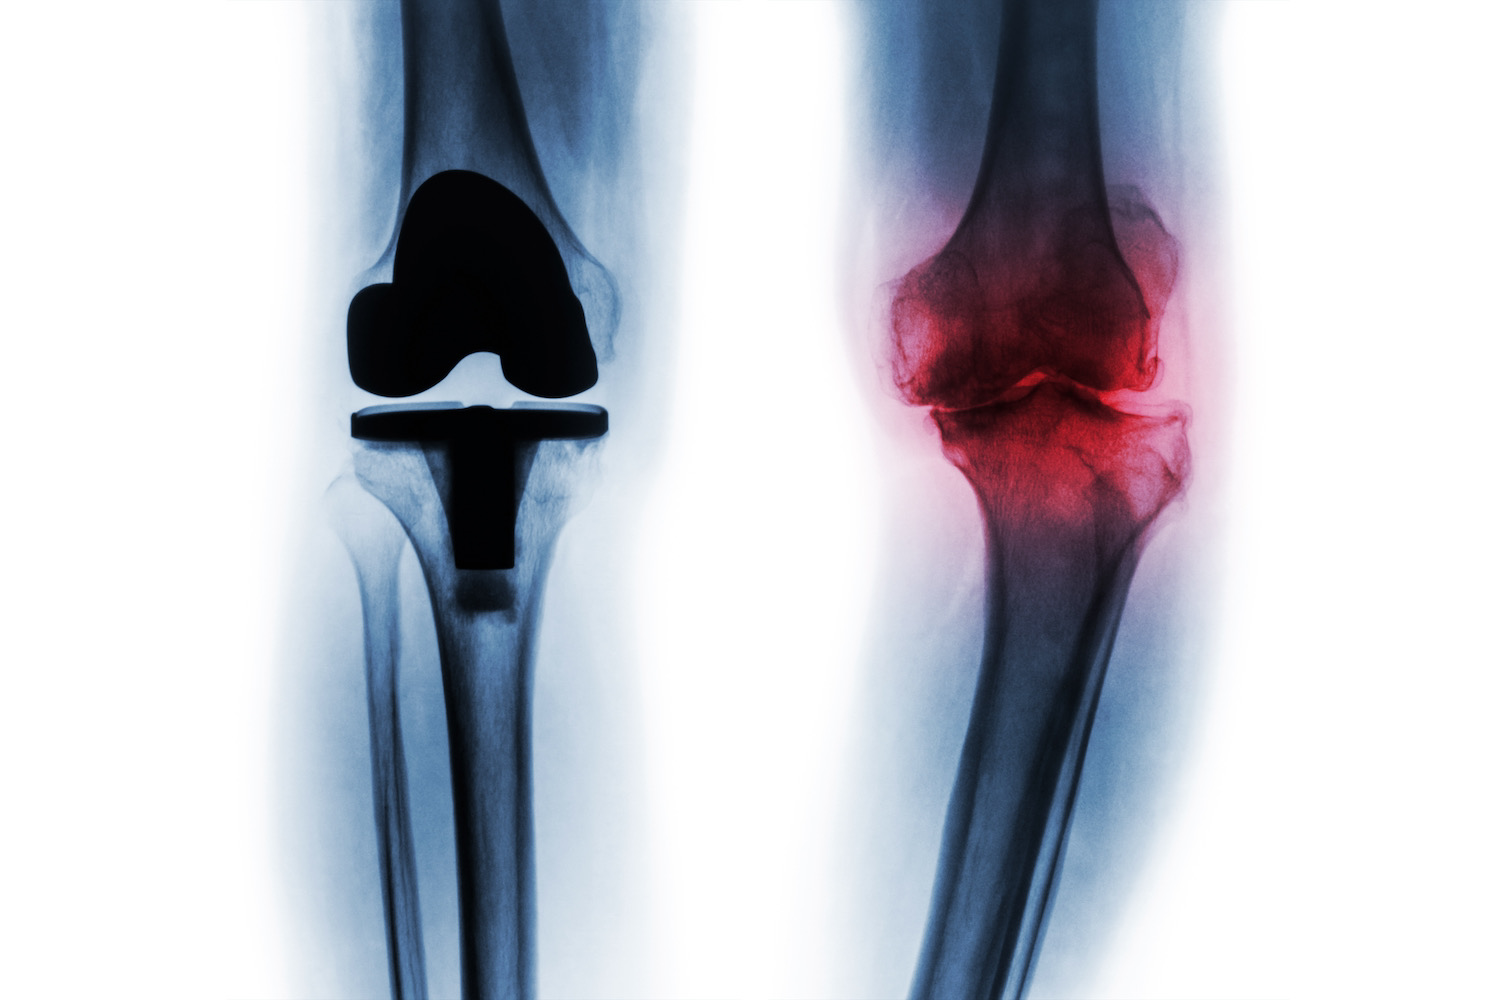

Something very important to understand is that the knee replacement procedure is the same whether you are in the United States or if you come to Monterrey México to get it. On a knee replacement, the surgeon cuts the damaged bone and cartilage from the shin and kneecap and replaces it with an artificial joint or prosthesis. During a total knee replacement, the damaged joint is completely removed and replaced with a prosthesis made of high-quality metal, ceramic, or plastic, as well as other polymer components.

Preparation: We prepare the bone by removing the cartilage surfaces at the end of the femur and tibia, along with a tiny amount of underlying bone.

Implant Placement: The removed cartilage and bone are replaced with metal components to recreate an articulating surface. The metal parts are cemented or "snapped" into the bone.

Patella Rejuvenation The underside of the patella, or the whole patella itself, can be cut and resurfaced with a special plastic component

Spacer insertion The surgeon will insert a medical-grade special plastic between the metal components of your new knee to create a very smooth gliding surface, this is in order for you to walk easier and smoother.